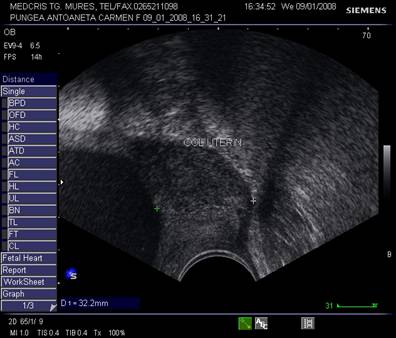

Fig. nr.234. Col uterin evaluat prin ecografie transvaginala , la o sarcina de 26 saptamani cu iminenta de nastere prematura prin contractii uterine, se remarca lungimea sa normala, canalul cervical si orificiul cervical intern inchis